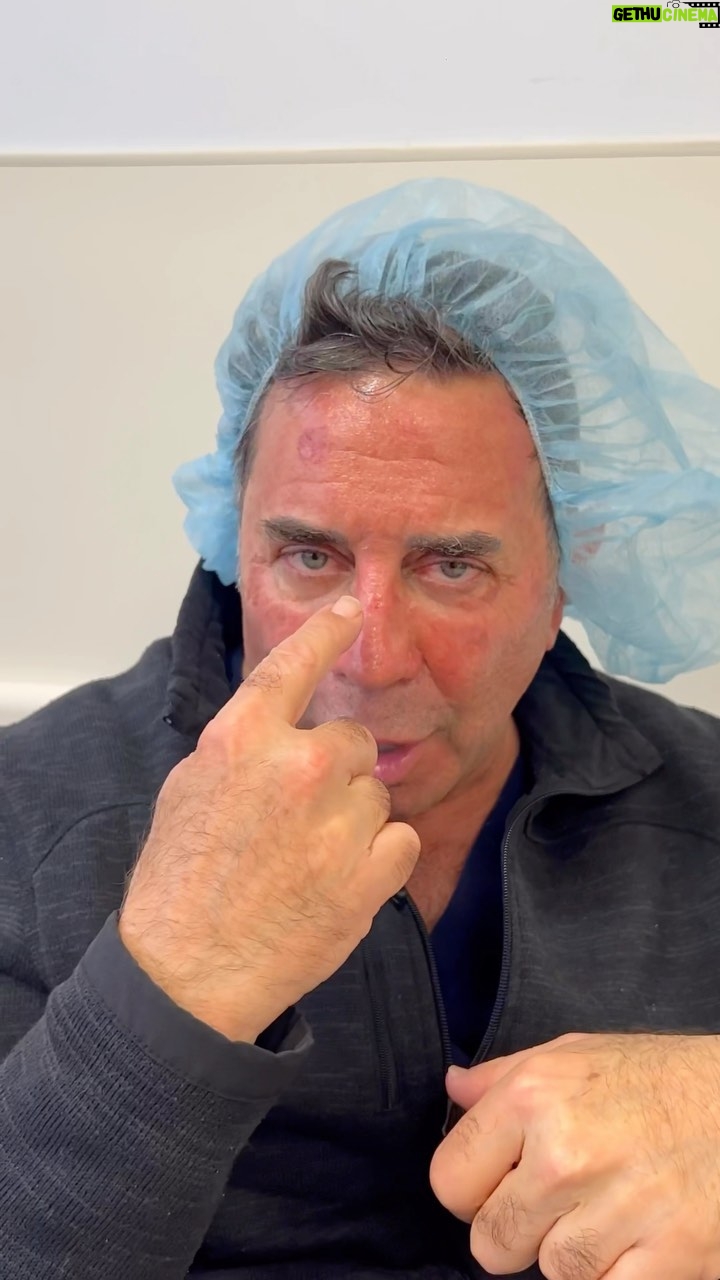

60.1K Likes – Paul Nassif Instagram

Caption : Skin Cancer Update! I know a lot of you wanted me to keep you updated, so here it is: Everything is going well so far after my procedures to remove the skin cancer. The worst side effect, as you can see, is the redness and uncomfortable dry skin from the laser treatments. Also, I’m going to start working on products and nutraceuticals that could help with DNA repair for those of us who have already done damage to our skin, but want to reduce the risk of getting skin cancer going forward. Thank you for all of the love and prayers; it means the world to me! I’ll continue to keep you updated and please remember to wear your sunscreen! ☀️🧴 🔊 Sound: On! #skincancer #awareness #prevention #sunscreen #dermatologist #surgery #updateLikes : 60094